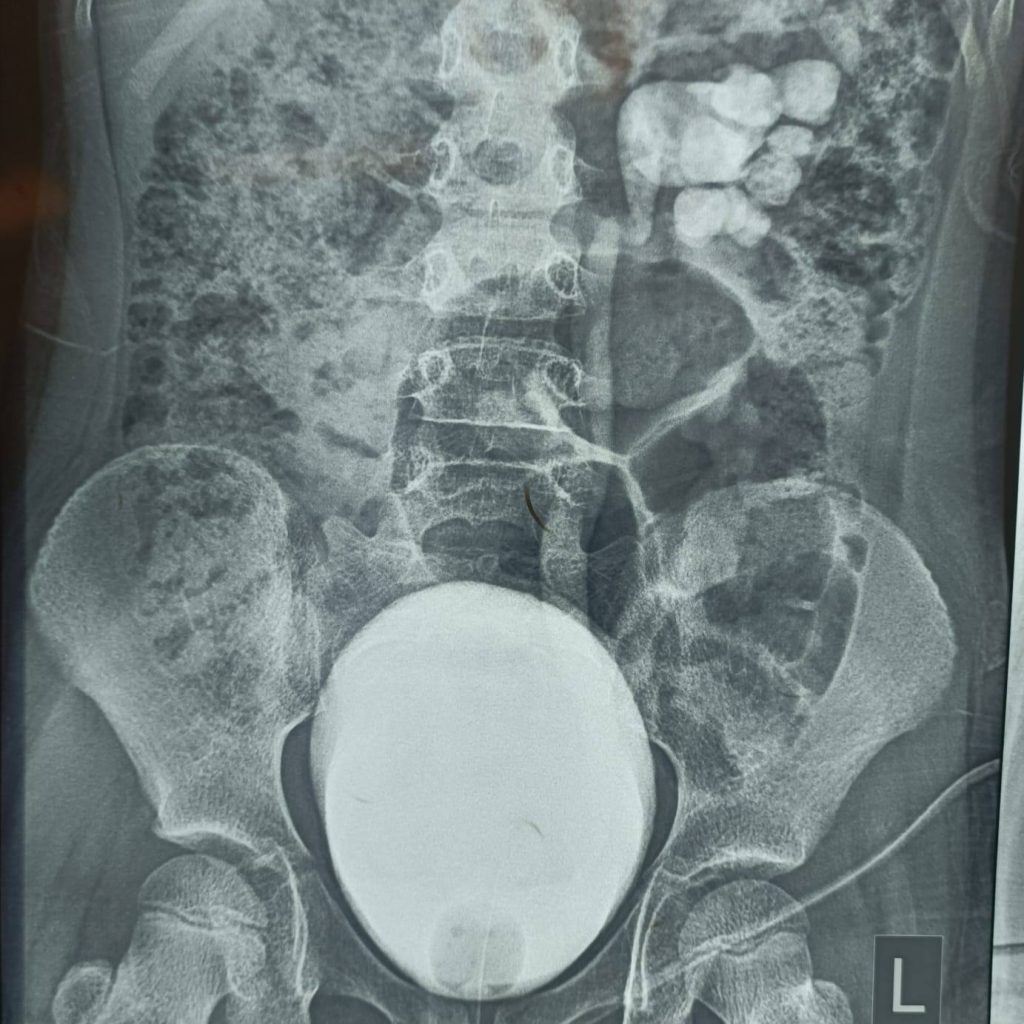

وأوضح الأعرجي أن الفحوصات السريرية والشعاعية كشفت عن تشوه خلقي نادر، مضيفًا:

“بيّن التقييم الطبي أن الكلية اليسرى كانت مقسومة إلى غرفتين منفصلتين، ولكل غرفة حالب مستقل يفتح في المثانة بفتحتين مختلفتين، وهي حالة غير شائعة وتخالف الكثير من الأنماط المسجلة في الأدبيات الطبية.”

وأشار إلى أن سبب المضاعفات كان خللًا وظيفيًا في الحالبين، موضحًا:

“كان الحالب العلوي يتسبب بارتداد البول من المثانة إلى الكلية، في حين كان الحالب السفلي يعاني من انسداد جزئي، ما أدى إلى استمرار الالتهابات والتوسع الكلوي.”

“خضعت الطفلة لعملية جراحية دقيقة استغرقت نحو ثلاث ساعات، تم خلالها إعادة زراعة الحالبين في المثانة بنجاح، مع الحفاظ الكامل على الغرف الكلوية دون أي مساس بوظيفتها.”